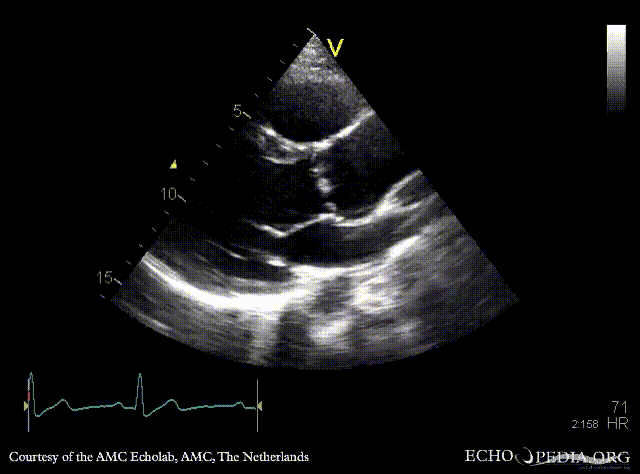

E00853.gif E00854.gif

PLAX: dilated aortic root and left ventricle PLAX with Color Doppler: severe aortic regurgitation